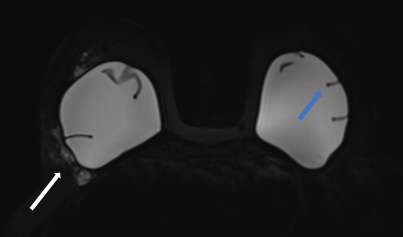

Intracapsular rupture with focal collapse of the outer shell will result in the “keyhole sign”, also referred to as the “noose sign”. This sign appears as a focal invagination of the hypointense outer shell where the two membranes do not touch. Similarly, the “teardrop sign” appears as a focal invagination of the hypointense outer shell containing a droplet of hyperintense extravasated silicone gel with the partial apposition of the two membranes13 (Figure 5).

Figure 5: Silicone-sensitive image shows hyperintense extracapsular silicone (white arrow) and keyhole sign (blue arrow).